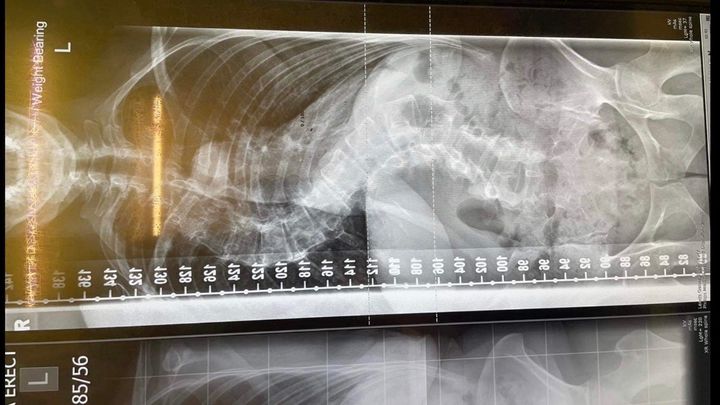

Kate was diagnosed with adolescent idiopathic scoliosis age 11 which has over the years progressed. Over the last few years it has become very serious with her S curves now measuring over 80 degrees.

Her spine has not only curved but caused rib rotation and she has now developed kyphosis. A recent MRI scan showed her spine is collapsing at the bottom. Her torso has collapsed also. She suffers debilitating daily pain.

The good news is that a top spinal surgeon at RNOH Stanmore hospital in Middlesex has taken Kate’s case on. This will mean two stage surgery. Firstly to block and cage the bottom of the spine that is collapsing. A week later a second surgery to fuse the rest of the spine with rods and screws going in from the front and opening the ribs. Due to the curves being left so long, it is likely they have auto-fused so she will not get a full correction, hopefully a little to regain some of the two inches she has lost in height over the last three years. Most importantly this surgery could be life saving as Kates organs are now compressed and breathing has become difficult.